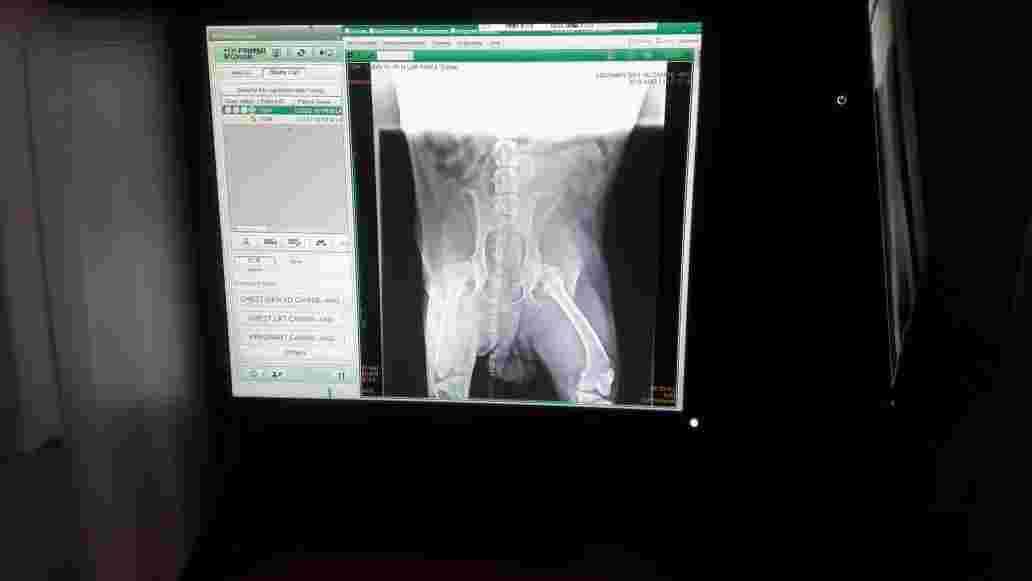

As you seen that attach xray my 7 yr labrador is eating but throwing up...doctor said he has pain in his leg I dont know what to do ? He lose 10 kg so please tell me is it life threatening or what because he is crying also i can see wet something coming out of eyes

Hi, thanks for using Petco Pet Education Center, formerly Petcoach! Did your vet take belly X-rays? If he is vomiting and has lost over 20 pounds. he needs X-rays of his belly and blood work. He does have very bad hips but that shouldn’t cause vomiting and weight loss. You need to follow up with your vet today. Good luck!